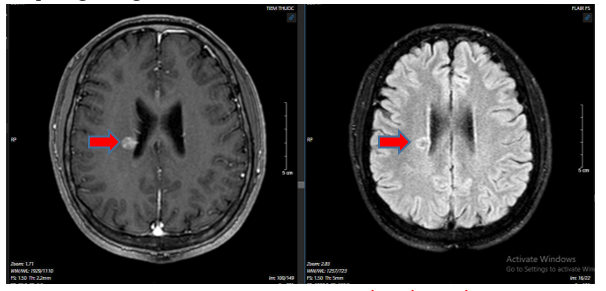

- Chụp cộng hưởng từ sọ não:

Hình 2: Hình ảnh cộng hưởng từ não có các nốt ngấm thuốc rải rác trong nhu mô trên và dưới lều, nốt lớn nhất vị trí cạnh não thất bên bên phải đường kính ~11mm (mũi tên đỏ), tín hiệu hỗn hợp trên FLAIR và T2W

Hình 5: So sánh phim chụp cộng hưởng từ sọ não trước điều trị so với phim chụp sau điều trị 4 tháng:  kích thước  khối u não cạnh não thất bên phải giảm từ 11mm xuống 5 mm. Phim chụp sau điều trị 8 tháng (hình không chứa mũi tên), không thấy khối u bất thường trên phim cộng hưởng từ sọ não.